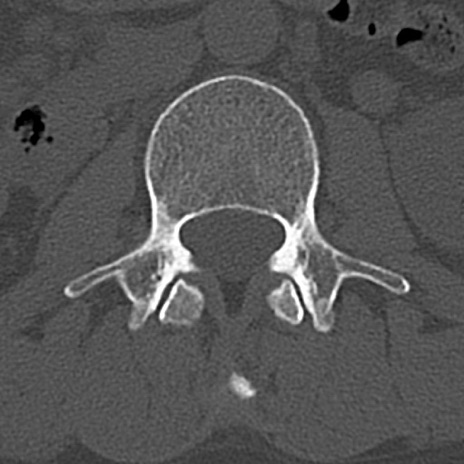

腰椎CT

横断像と矢状断像